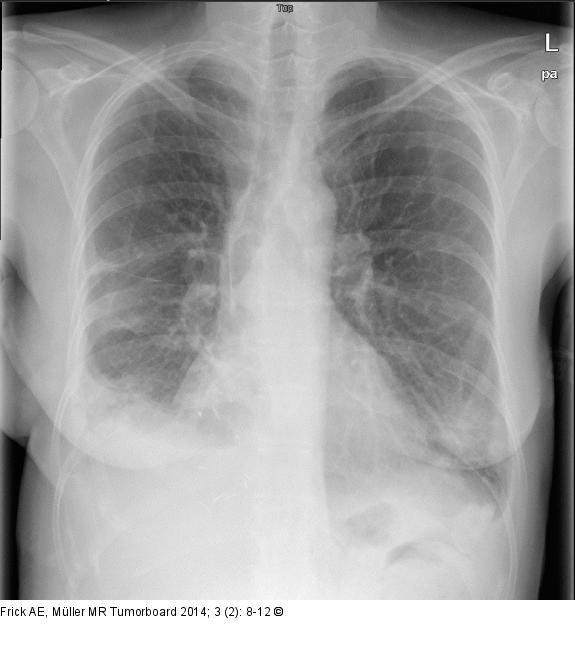

Abbildung 4b: Biphasisches Synovialsarkom Postoperative Röntgenübersicht im Stehen: Ausgedehnte Lunge beidseits mit kleinem Randwinkelerguss rechts |

Postoperative Röntgenübersicht im Stehen: Ausgedehnte Lunge beidseits mit kleinem Randwinkelerguss rechts |